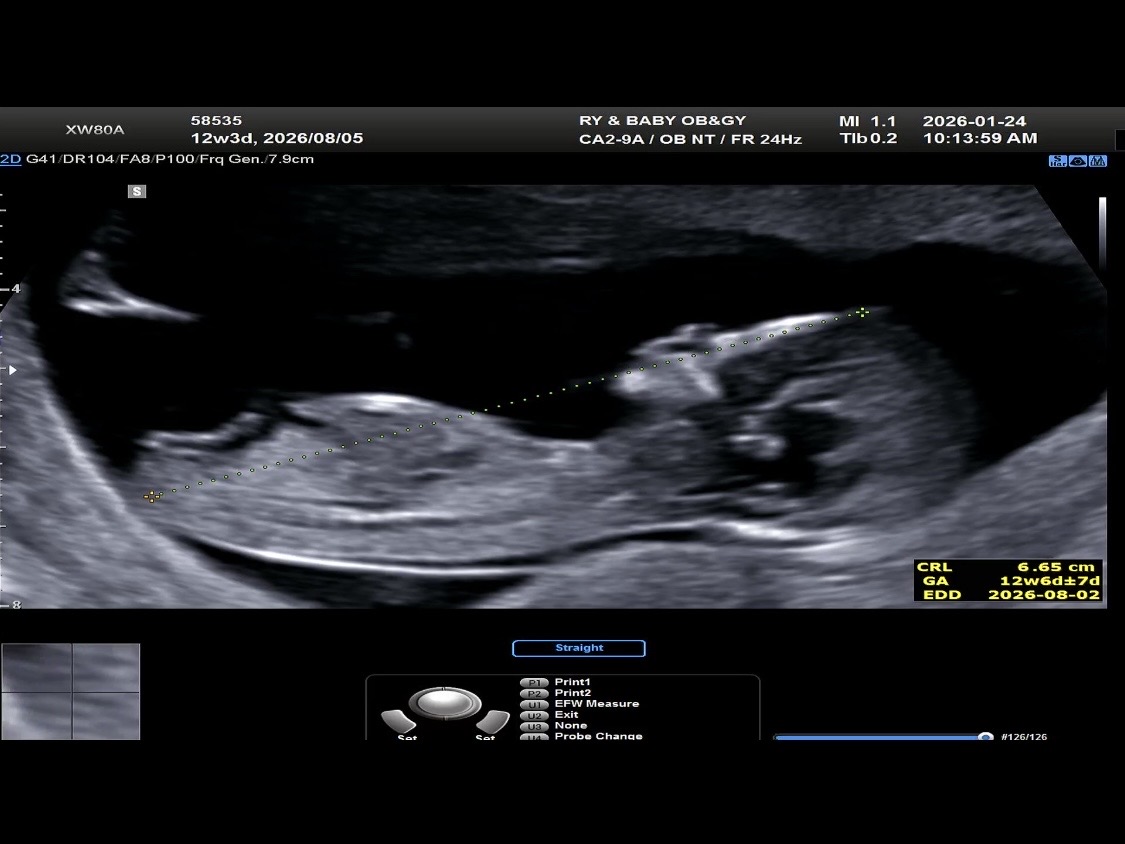

12주 아들 딸 각도법 봐주세요🥹🫶🏻

각도법 봐주세요!!